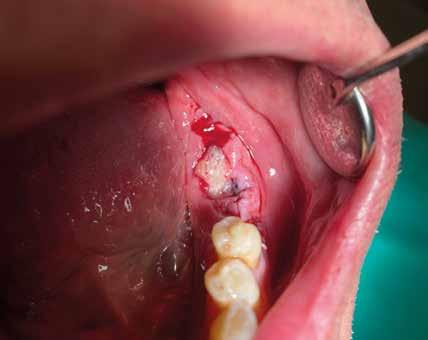

2. Estrazione dentaria (Figg. 3-6)

Estrazione di 3 elementi dentari complicata da frattura coronale di 2.4 e presenza di 2 corone protesiche unite su denti pluriradicolati. L’approccio deve prevedere la rimozione delle corone protesiche e la separazione delle radici, semplificando le manovre di estrazione e consentendo di risparmiare i tessuti molli pericoronali e prevenire la frattura

Il rispetto dei tessuti molli consente di ridurre i tempi di guarigione, sebbene a siti più ampi corrisponda un tempo di ripristino o maggiore. Il mantenimento delle corticali vestibolari, palatine e l’assenza di alveolite post-estrattiva riducono l’atrofia ossea.

FIG. 2 FIGG. 5,6: FIG. 5 FIG. 6 FIGG. 3,4: delle corticali ossee più sottili. FIG. 3 FIG. 4